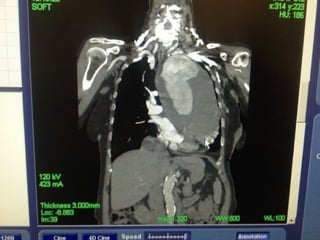

• Preoperative CT 1mm imaging to include pelvisPreoperative CT 1mm imaging to include pelvis